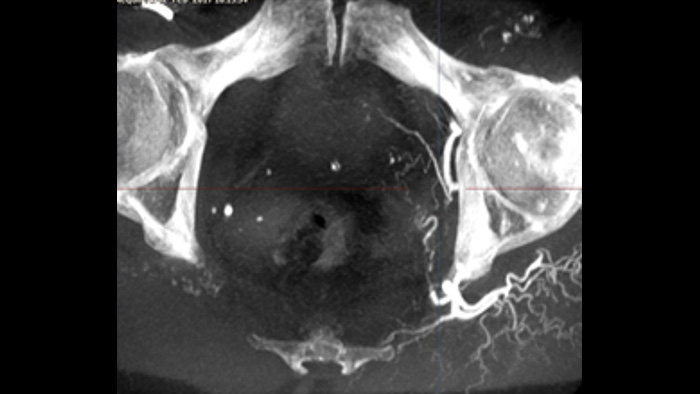

SmartCT Soft Tissue ofrece una técnica de adquisición de tomografía de haz cónico (THC) aumentada con guía paso a paso, visualización 3D avanzada y herramientas de medición, todo accesible en el módulo de pantalla táctil desde la mesa. Para ayudarle a adquirir imágenes de THC correctas a la primera y agilizar su flujo de trabajo, se le guía a través de los pasos clave.